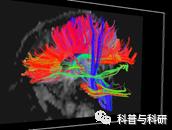

(3)基于ROI-ROI的概追性纤维追踪分析

1 弥散张量数据的预处理

2 ROI的提取和空间转换

3弥散方向分布估计BedPostX

4 概率性纤维追踪

5 概率追踪结果的量化统计